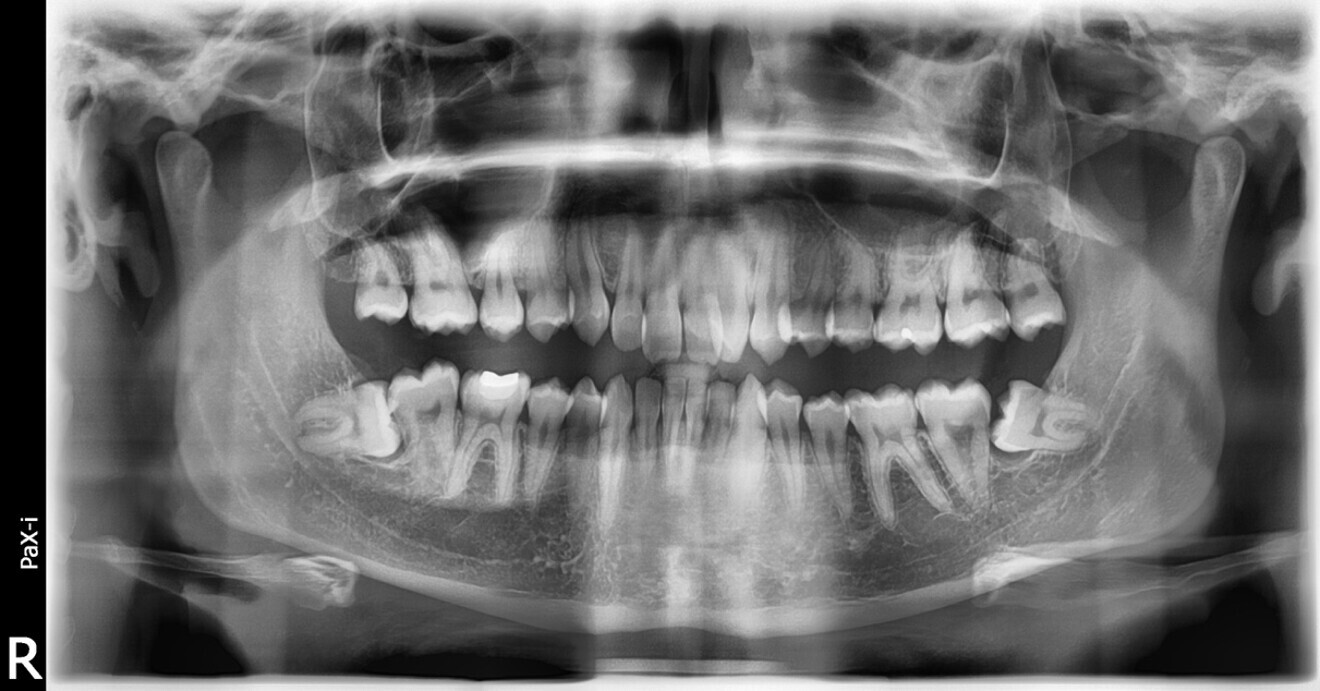

In the radiographic analysis, the dental panoramic tomogram revealed that the two mandibular third molars were unerupted and horizontalised in the mandible. Nothing else relevant was observed in the radiograph (Fig. 3). A cephalometric radiograph was used to perform the cephalometric analysis according to Steiner,6 Ricketts7, 8 and McNamara9 (NemoCeph Studio, Nemotec Fig. 4).

Fig. 3: Dental panoramic tomogram.